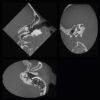

- Phẫu thuật miệng hàm mặt: lên kế hoạch cắt xương, u nang, u xương hàm

- Đánh giá TMJ: hình ảnh lồi cầu 3D, không gian khớp